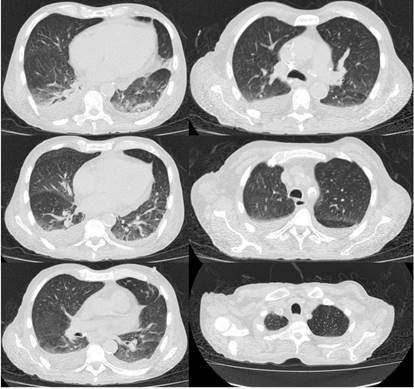

Ingresó por un cuadro clínico de 9 meses de evolución consistente en pérdida de peso de aproximadamente 12 kg, sudoración nocturna, astenia, adinamia y tos ocasionalmente productiva en el último mes. Adicionalmente, manifestó tener deposiciones diarreicas sin moco ni sangre, aproximadamente de 4 a 5 deposiciones al día durante 4 días antes del ingreso, la cual resolvió por sí mismo con hidratación y medidas generales. Al ingreso se documentó fiebre en 38,3 °C, palidez generalizada y taquicardia; y los exámenes de laboratorio iniciales documentaron leucopenia, anemia de volúmenes bajos en criterios de transfusión, trombocitopenia, hiponatremia leve hipovolémica hipoosmolar, hipomagnesemia e hipoalbuminemia (Figura 1 y Tabla 1). En el estudio de tomografía de tórax se obtuvieron hallazgos compatibles con silicoantracosis e imágenes hipodensas en las vértebras de carácter inespecífico (Figura 2).